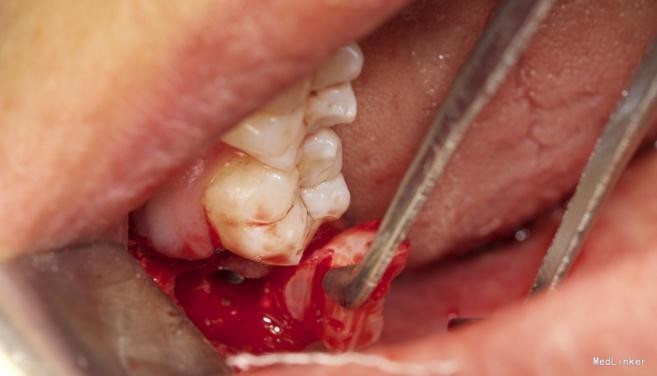

左下8水平阻生拔除

拔除术

患者,男,25岁,要求拔除左下颌水平阻生牙齿,平素体质一般,无药物、食物过敏史,无高血压、心脏病等系统病史